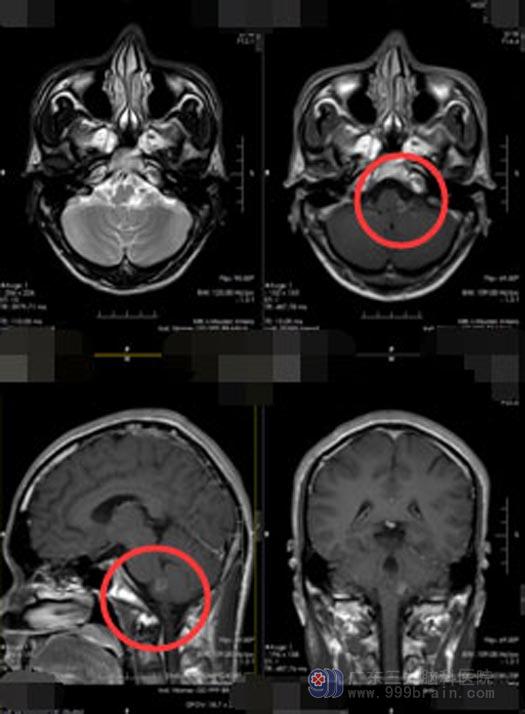

为寻求进一步的治疗,许先生来到了广东三九脑科医院。头颅MR检查发现:“左侧桥脑-小脑上角占位性病变”。桥小脑角三角区是一锥形立体三角,它在后颅窝的前外侧,由前内侧的桥脑外缘、前外侧的岩骨内缘及后下方的小脑半球前外侧缘构成一个锥形窄小的空间,而锥交则正于岩骨尖,此区的重要性在于集中了听神经、面神经、三叉神经及岩静脉、小脑前上动脉等。此区若出现听神经瘤或脑膜瘤等,便会逐渐损害上列组织而产生桥小脑角区综合征,其临床表现为:持续性耳鸣,眩晕、面部感觉缺失、疼痛、同侧角膜反射减弱和消失等。结合患者之前的症状和体征,医院副院长、神经外五科主任鲁明建议行手术治疗。

患者及家属知情同意后,由鲁明主刀在全麻下行“延髓、脑桥左侧-左侧小脑上角病变切除术”,后颅窝导航定位,取后正中切口,术中导航再次定位,切除左侧小脑上角及左侧延髓-脑桥病变组织,术区无出血,手术顺利。